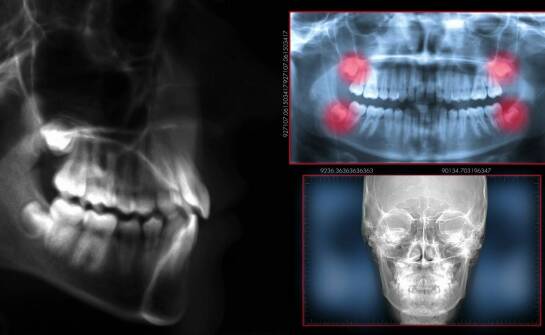

Licówki to cienkie nakładki stosowane w stomatologii estetycznej, które znacząco poprawiają wygląd zębów. Dzięki nim pacjenci mogą cieszyć się pięknym uśmiechem, co przekłada się na większą pewność siebie. Warto zaznaczyć, że dostępne są różne rodzaje licówek, takie jak porcelanowe czy kompozytowe,